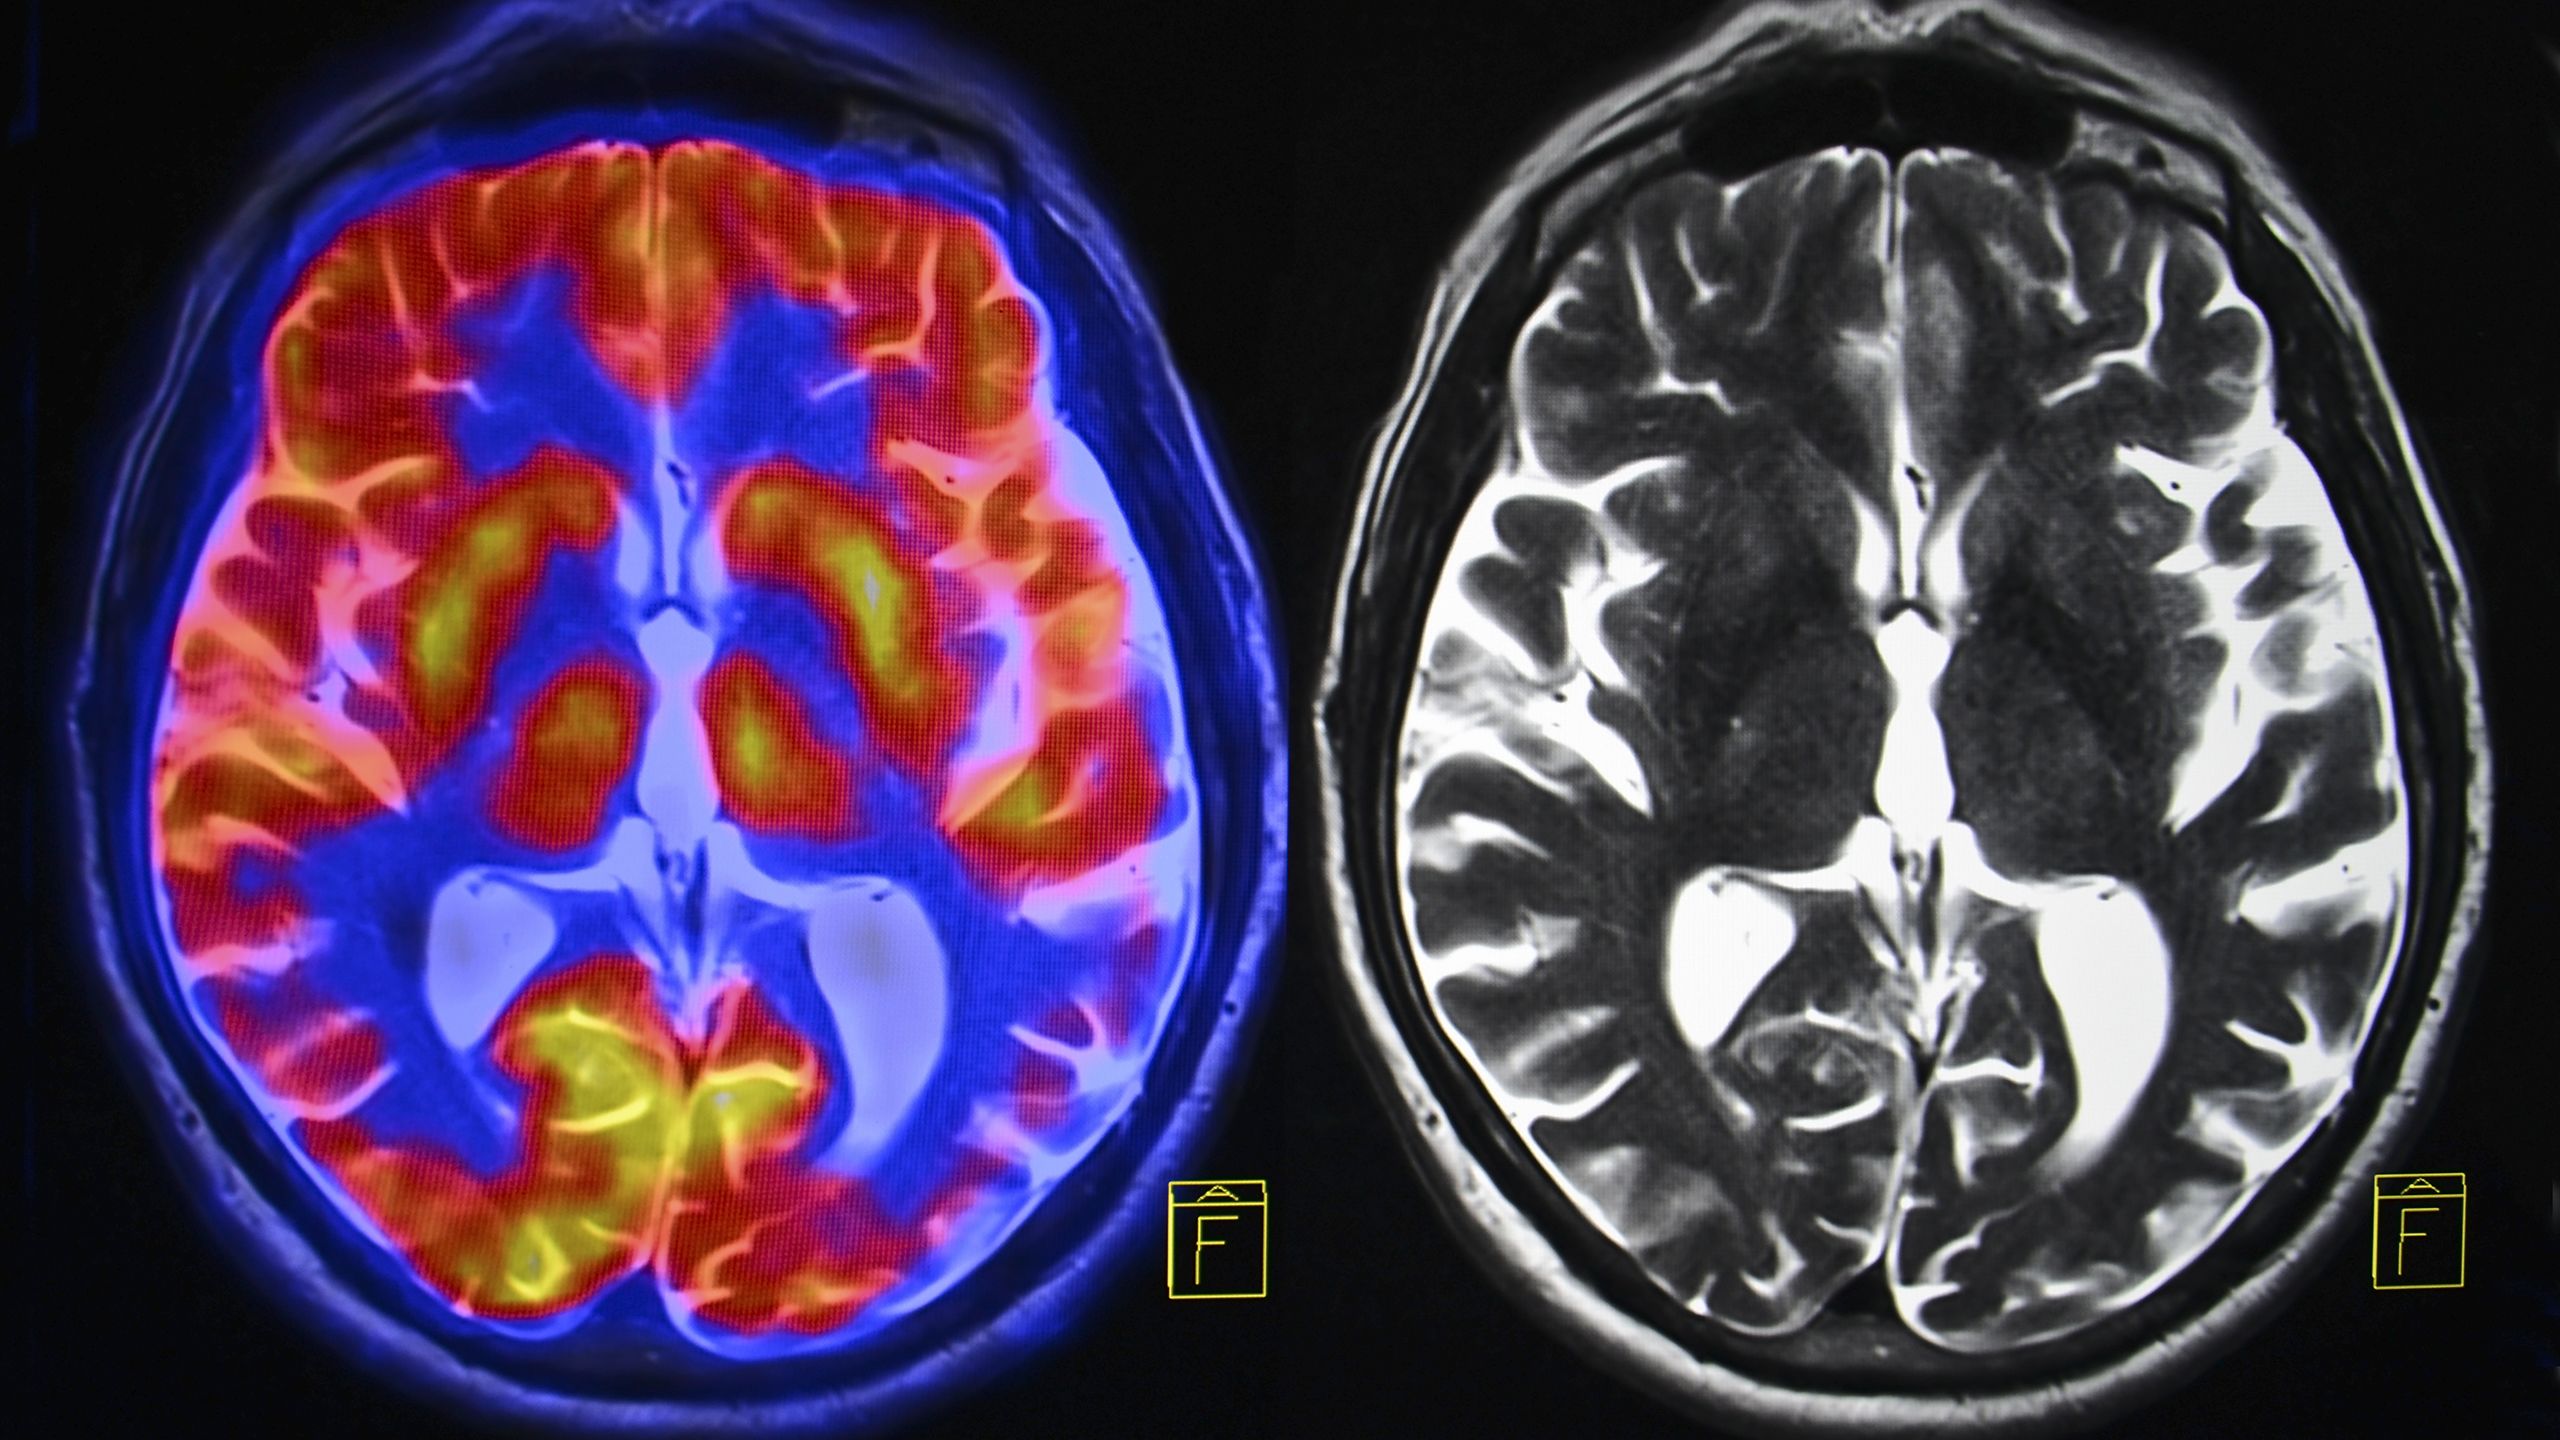

The NHS advises that most adults need between 6 and 9 hours of sleep every night. We still don’t know exactly why we sleep, but we do know that poor sleep can have a detrimental effect on our health. There are various theories on why sleep is needed, although no scientific consensus. These include:

- To reset connections between brain cells

- To process information from the previous day

- To clear damaged proteins and waste from the brain